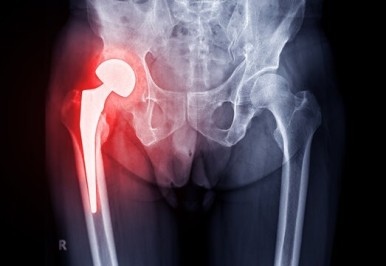

고관절(엉덩관절)은 골반과 대퇴골(넙다리뼈)이 연결되는 관절입니다.

골반을 통해 체중을 지탱하고 걷기,달리기, 다리 들어 올리는 힘 등등 안정성이 우선시 되는 부위입니다.

특히 걷거나 뛸때에는 굉장한 하중을 받기 때문에 이 관절이 중요한 이유 중 하나입니다.

안정성이 떨어진다면 기능적인 문제는 물론 질환에 노출될 가능성이 높아집니다.

고관절에 문제가 생기면 관절염, 고관절염증, 더불어 혈액순환의 문제, 골반틀어짐,

근육의 비정상적 단축 등 문제가 나타나겠지요.

움직임에 따라 고관절에 지속되는 통증이 있다거나 가동범위가 제한적이라면

염증이 나타나있을 확률이 있으니 병원에 방문하여 검진해보는것을 추천드립니다.